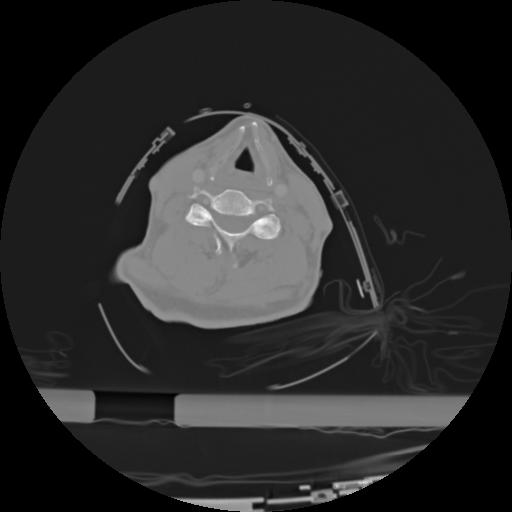

21 ANGIO,CE,Axial,3.0,ANGIO,,